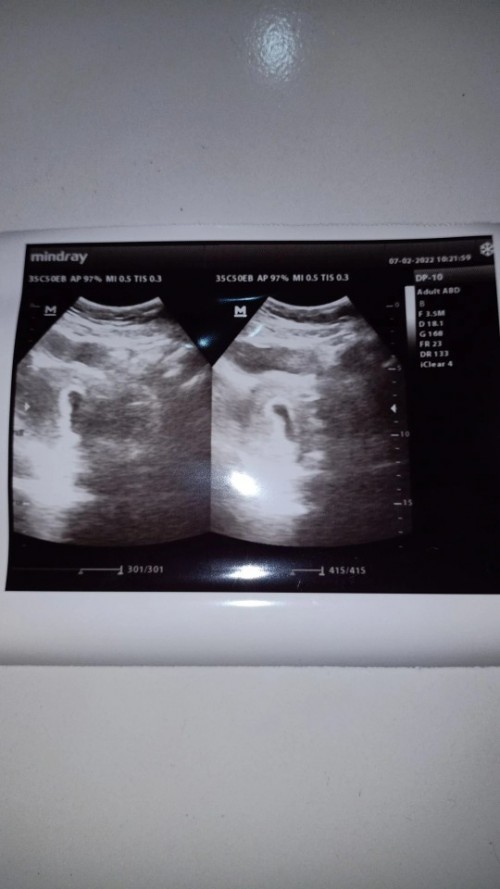

kantung bayi

Bun sy mau tanya, normalkah hamil 6 minggu baru kliatan kantung.a aja atau bagaimana ? Dan ukurannya baru 2cm bun, normalkah ?

4-6 minggu biasanya janin baru sebutir beras ukurannya bun, mungkin ukuran kantungnya ya bun yg 2 cm ?

ada yg blg normal bun kata biasa d suruh dtg lg seminggu kemudian. btw gede banget 2cm bun?? 2mm kali

hamil 6 minggu ini tuh kantungnya mirip sama janin kecil yah . atau ini memang kantung saja bun ?